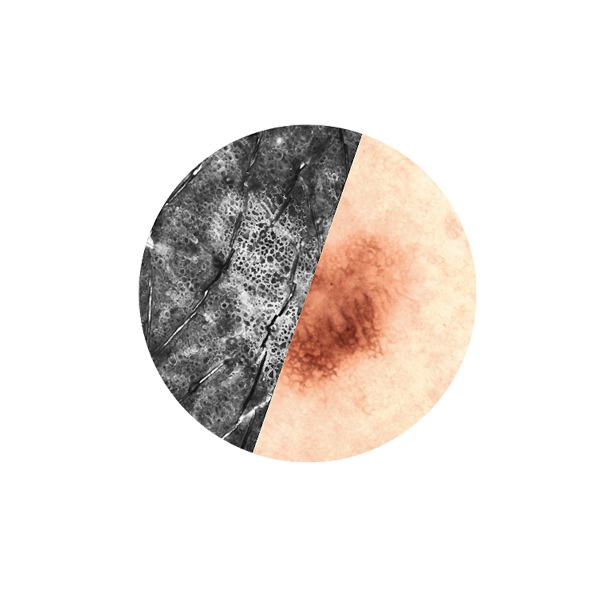

In Vivo examinations with the VivaScope technology using confocal laser scanning microscopy (CLSM) allow for an optical biopsy using a non-invasive procedure. See the different skin layers of your patients in real time.

All images courtesy of Prof. Dr Elke Sattler, Dr Martina Ulrich, Prof. Dr Julia Welzel